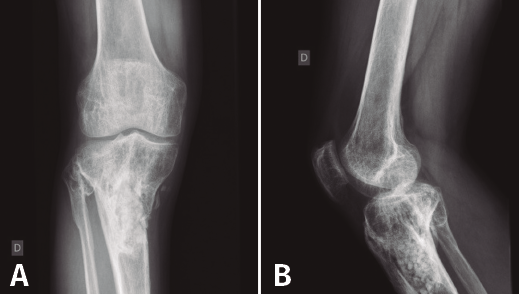

Figura 5. Radiografías de frente y de perfil del extremo proximal de la tibia donde se objetiva la cavidad en la tibia con presencia de material granulado en su interior.

En el estudio radiológico (Figura 5) se objetiva imagen cavitaria en el extremo proximal de la tibia con presencia de material granulado del injerto realizado.